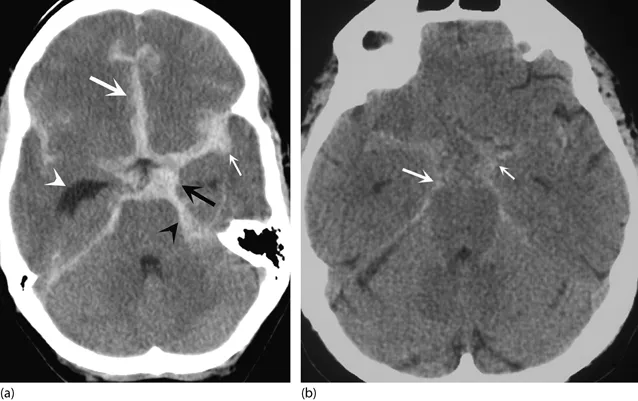

Intracranial Hemorrhages - The Bleeding Brain

| CT Appearance | Biconvex (lentiform) 📌 Lemon; hyperdense. Does NOT cross sutures. | Crescentic 📌 Banana; hyperdense (acute), isodense (subacute), hypodense (chronic). CAN cross sutures. | Hyperdense in sulci, cisterns, fissures. | Hyperdense areas; coup/contrecoup injuries. |

- Intraventricular Hemorrhage (IVH): Blood within ventricles. Often indicates severe injury and poorer prognosis. Can be an extension from tSAH or ICH.

- CT Density: Acute blood is hyperdense (~60-80 HU).